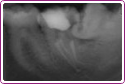

Ząb Pana Andrzeja wymagał leczenia kanałowego. Kanały były zakrzywione. Na zdjęciu efekt 30 min pracy.